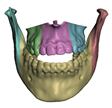

2.5.1. Bones

2.5.2. Soft Tissue

- In maxillary procedures, the maxilla is separated from the skull through a Lefort osteotomy, classified based on its anatomical level. In this cohort, the distribution of cases is: 8 Lefort I cases and 1 Lefort II case; one patient did not undergo maxillary surgery. Moreover, after a Lefort I osteotomy, the maxilla may be segmented (typically into three fragments) in order to expand the upper arch. Maxilla segmentation was applied to 6 patients in this cohort.

- In mandibular procedures, the mandible may be sagittally split on both rami (bilateral sagittal split osteotomy, BSSO) or only one ramus (unilateral sagittal split osteotomy, USSO). In this cohort, the distribution of cases is: 7 BSSO cases, 1 USSO case; two patients did not undergo mandibular surgery. Additionally, a chin osteotomy or genioplasty may be also performed. Genioplasty was applied to 1 patient in this cohort.